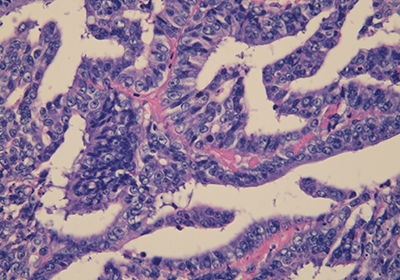

病理・細胞診検査

細胞診標本【Papanicolaou染色】…腺がん

細胞診標本【PAS染色】…腺がん

病理組織標本【HE染色】…大腸がん病変部位